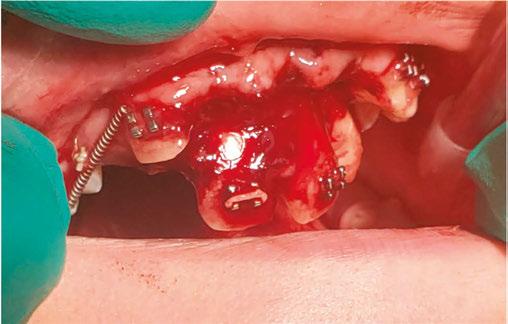

Luckily, the young boy was undergoing orthodontic treatment so the avulsed teeth remained in the oral cavity. As you can see from the clinical photograph in Figure 1, teeth Nos. 8, 9, and 10 would not have remained in the mouth if the orthodontic wire was not in place.

Two days after treatment, the patient was seen in my practice after the teeth were splinted back in place by the orthodontist. Figures 2A-2B are the preoperative radiographs after the teeth were reimplanted.

One can already appreciate the inflammatory resorption that is occurring at the apices of teeth Nos. 9 and 10. These images were taken just two days after the trauma.

My goal at the first visit was to understand the trauma with respect to the extraoral dry time of the teeth (how long were

Figure 1

Figures 2A-2B